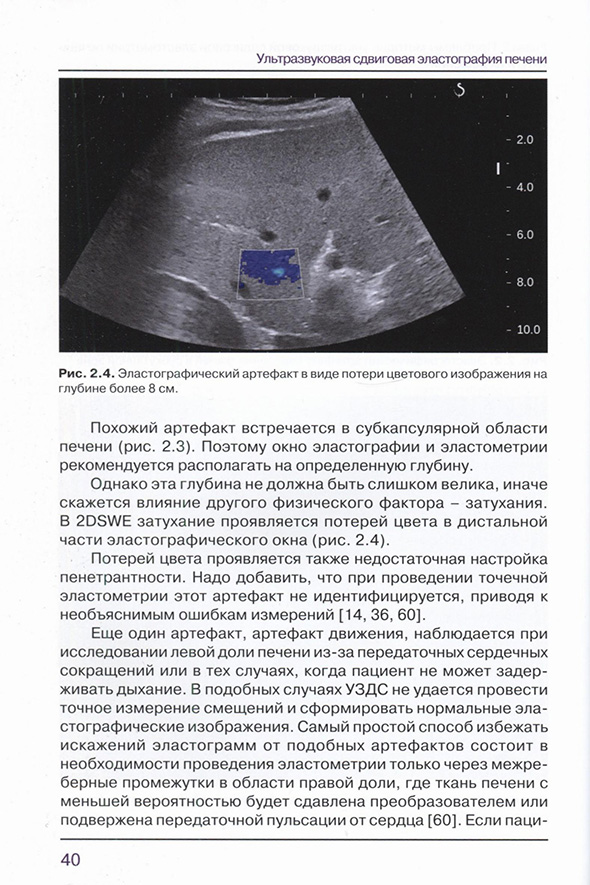

1.2.2.2. Двумерная сдвиговая эластография и эластометрия (2DSWE)